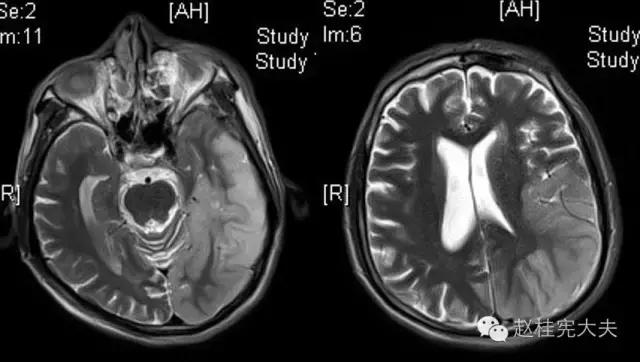

完善检查,头颅MRI回报:左侧颞顶枕叶急性梗死灶。

当看到磁共振片子的时候,我知道,我们轻忽了一些东西......

患者的磁共振影像不符合脑血管病的血供分布,跨了大脑中动脉和大脑后动脉范围,且病灶偏皮层分布。大脑前、中、后动脉血供分布(横断面)见下图